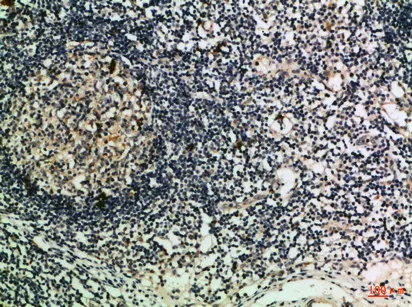

MCP-3 Rabbit Polyclonal Antibody

Cat: APRab13734

Size1:50μl Price1:$118

Size2:100μl Price2:$220

Size3:500μl Price3:$980